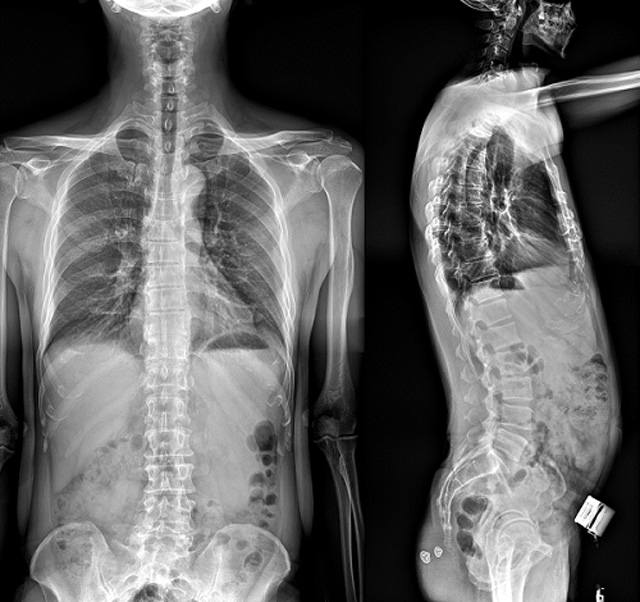

(7)全身拼接功能對有較大尺寸全脊柱拼接圖接桂成金下股分成幾次拍攝,再經(jīng)過秋件開在骨科開展的全脊柱畸形矯治工作中,雖然CT. MRI也能獲取全脊柱影像,接圖像,以便于長度、角度、力線等測量和察脊柱在重力情況下但不能進(jìn)行立位檢查,無法觀全景觀察。全身拼接功能是高等級DR攝取患者立位全下的功能狀態(tài)圖像,因此采用動態(tài)醫(yī)院特別看重的動態(tài)DR功能之一。注:圖中Cobb脊柱正側(cè)位圖像是首選的檢查方法角度的大小是反映側(cè)彎嚴(yán)重程度的一個(gè)標(biāo)準(zhǔn)。